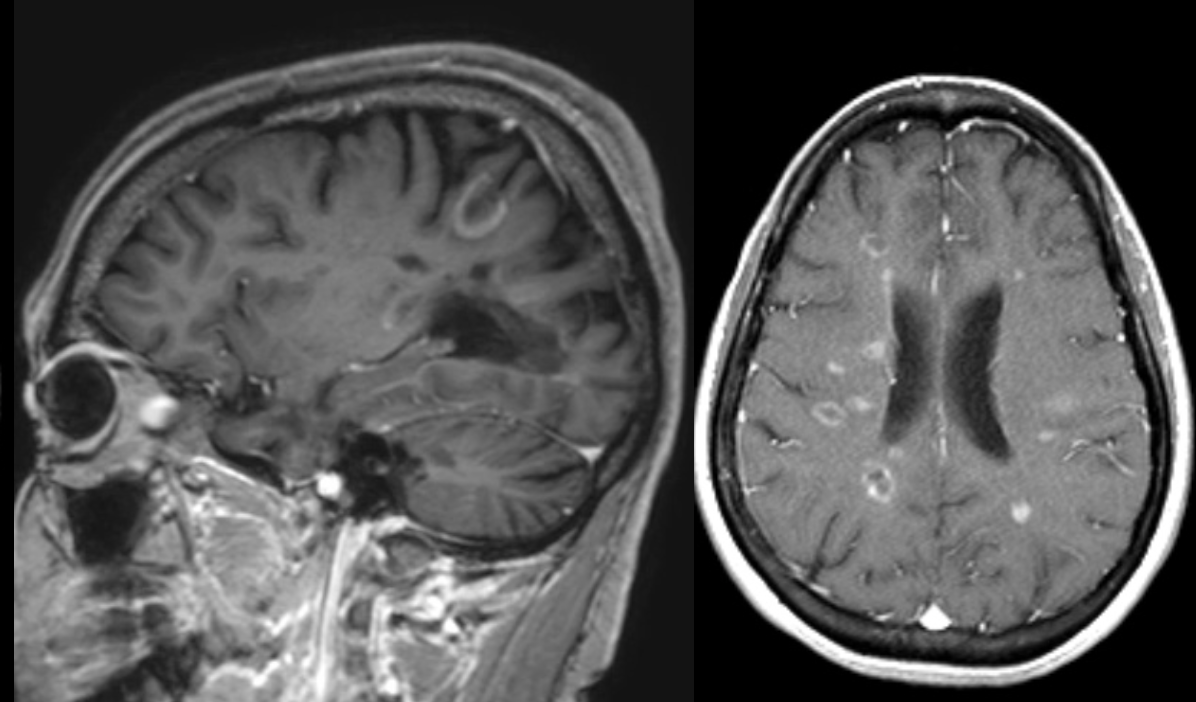

A 34 year-old patient presented with double vision and left arm weakness.

Multiple sclerosis - incomplete ring-enhancing lesions